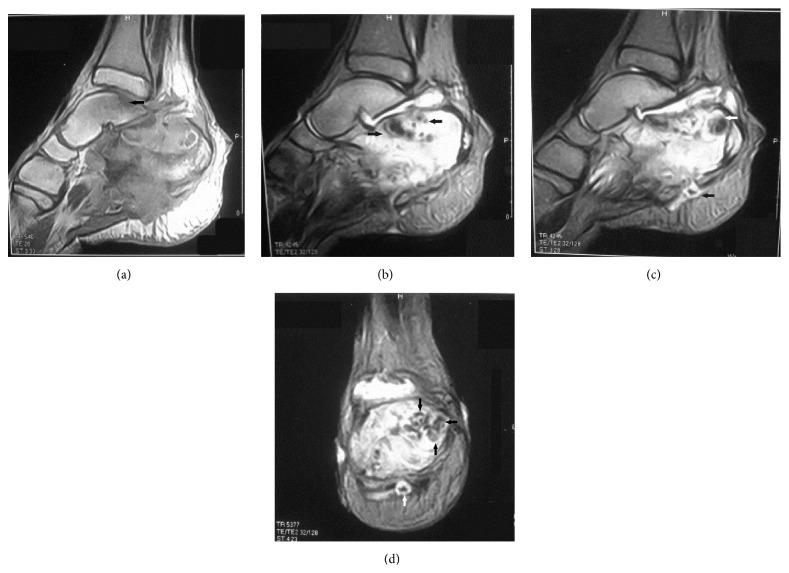

Fungi are unusual causes of pedal osteomyelitis in children and adolescents. Eumycetoma is a chronic cutaneous and subcutaneous infection caused by various genera of fungi. A provisional diagnosis of foot mycetoma is made after clinical assessment. Radiologic-pathologic correlation is an essential supplement for the accurate diagnosis of osteoarticular infections. This paper aims to sensitize orthopedic surgeons, radiologists, and pathologists to the importance of correlative imaging findings in relation to surgical and microscopic pathology in osteoarticular infections, specifically eumycetoma osteomyelitis of the foot. From our review of the published data, the present case is the first report of radiologic-pathologic correlation in eumycetoma osteomyelitis of the calcaneus. This paper describes a case of eumycetoma osteomyelitis of the calcaneus in a child in which diagnostic X-rays and magnetic resonance imaging (MRI) were correlated with the surgical and microscopic pathologic features, for establishing an appropriate diagnosis and treatment. We conclude that there is a significant agreement between radiologic and pathologic evaluation for assessment of eumycetoma osteomyelitis of the calcaneus. Radiologic-pathologic correlation amplified our interpretation of imaging information available on plain radiographs and MRI and augmented diagnostic confidence. Similarly, anatomic-histopathological correlations consolidated diagnostic accuracy.

真菌是儿童和青少年足部骨髓炎的不常见病因。足菌肿是一种由多种真菌属引起的慢性皮肤和皮下感染。临床评估后作出足部足菌肿的初步诊断。放射学与病理学的相关性是准确诊断骨关节感染的重要补充。本文旨在使骨科医生、放射科医生和病理科医生认识到在骨关节感染,特别是足部足菌肿性骨髓炎中,相关影像学表现与手术及显微镜下病理学之间关系的重要性。通过我们对已发表数据的回顾,本病例是跟骨足菌肿性骨髓炎放射学与病理学相关性的首例报道。本文描述了一名儿童跟骨足菌肿性骨髓炎病例,其中诊断性X线和磁共振成像(MRI)与手术及显微镜下病理特征相关联,以确立适当的诊断和治疗方法。我们得出结论,在评估跟骨足菌肿性骨髓炎时,放射学和病理学评估之间存在显著一致性。放射学与病理学的相关性增强了我们对平片和MRI上可用影像信息的解读,并提高了诊断信心。同样,解剖学与组织病理学的相关性巩固了诊断准确性。